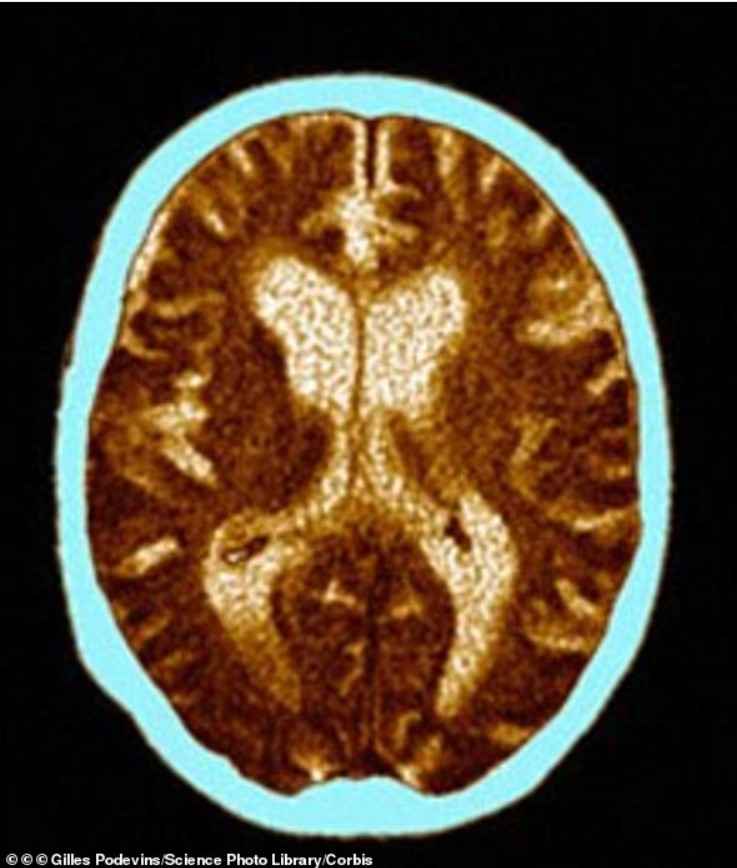

Rrudhat e fytyrës – veçanërisht ato rreth syve, të njohura si “këmbët e sorrës” – mund të jenë një sinjal i hershëm i rrezikut për zhvillimin e sëmundjes së Alzheimerit dhe formave të tjera të demencës, sugjeron një studim i ri shkencor.

Studiues në Kinë kanë zbuluar se personat që perceptohen se duken më të vjetër sesa mosha e tyre reale kanë mbi 60 për qind rrezik më të lartë për t’u diagnostikuar me demencë brenda 12 viteve, edhe pasi u morën parasysh faktorë si shëndeti dhe stili i jetesës. Demenca prek aktualisht rreth 7 milionë persona vetëm në SHBA.

Në një analizë të dytë, të publikuar në të njëjtin raport, u zbulua se njerëzit me më shumë rrudha rreth syve kishin më shumë se dyfishin e gjasave për dëmtime të matshme njohëse, krahasuar me ata që kishin më pak rrudha.